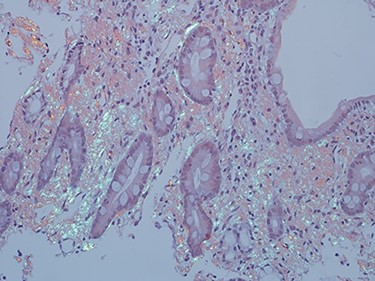

As work up for his abdominal pain and anemia he underwent gastroscopy on 29 October 2020 that revealed congested and nodular gastric mucosa (mass-like) and at lesser extend in the first and second part of duodenum (Figs 1 and 2). Biopsies were taken from the gastric lesion and duodenum. Histopathological findings from gastric mass and duodenum showed marked stromal hyalinosis, which appeared as a cellular pink material on H&E stain (Figs 3 and 5). Congo red stain (amyloid stain) showed apple green birefringence under polarized light on both gastric and duodenal biopsies (Figs 4 and 6).

High power of duodenal biopsy showing stromal hyalinosis (H&E x 20).